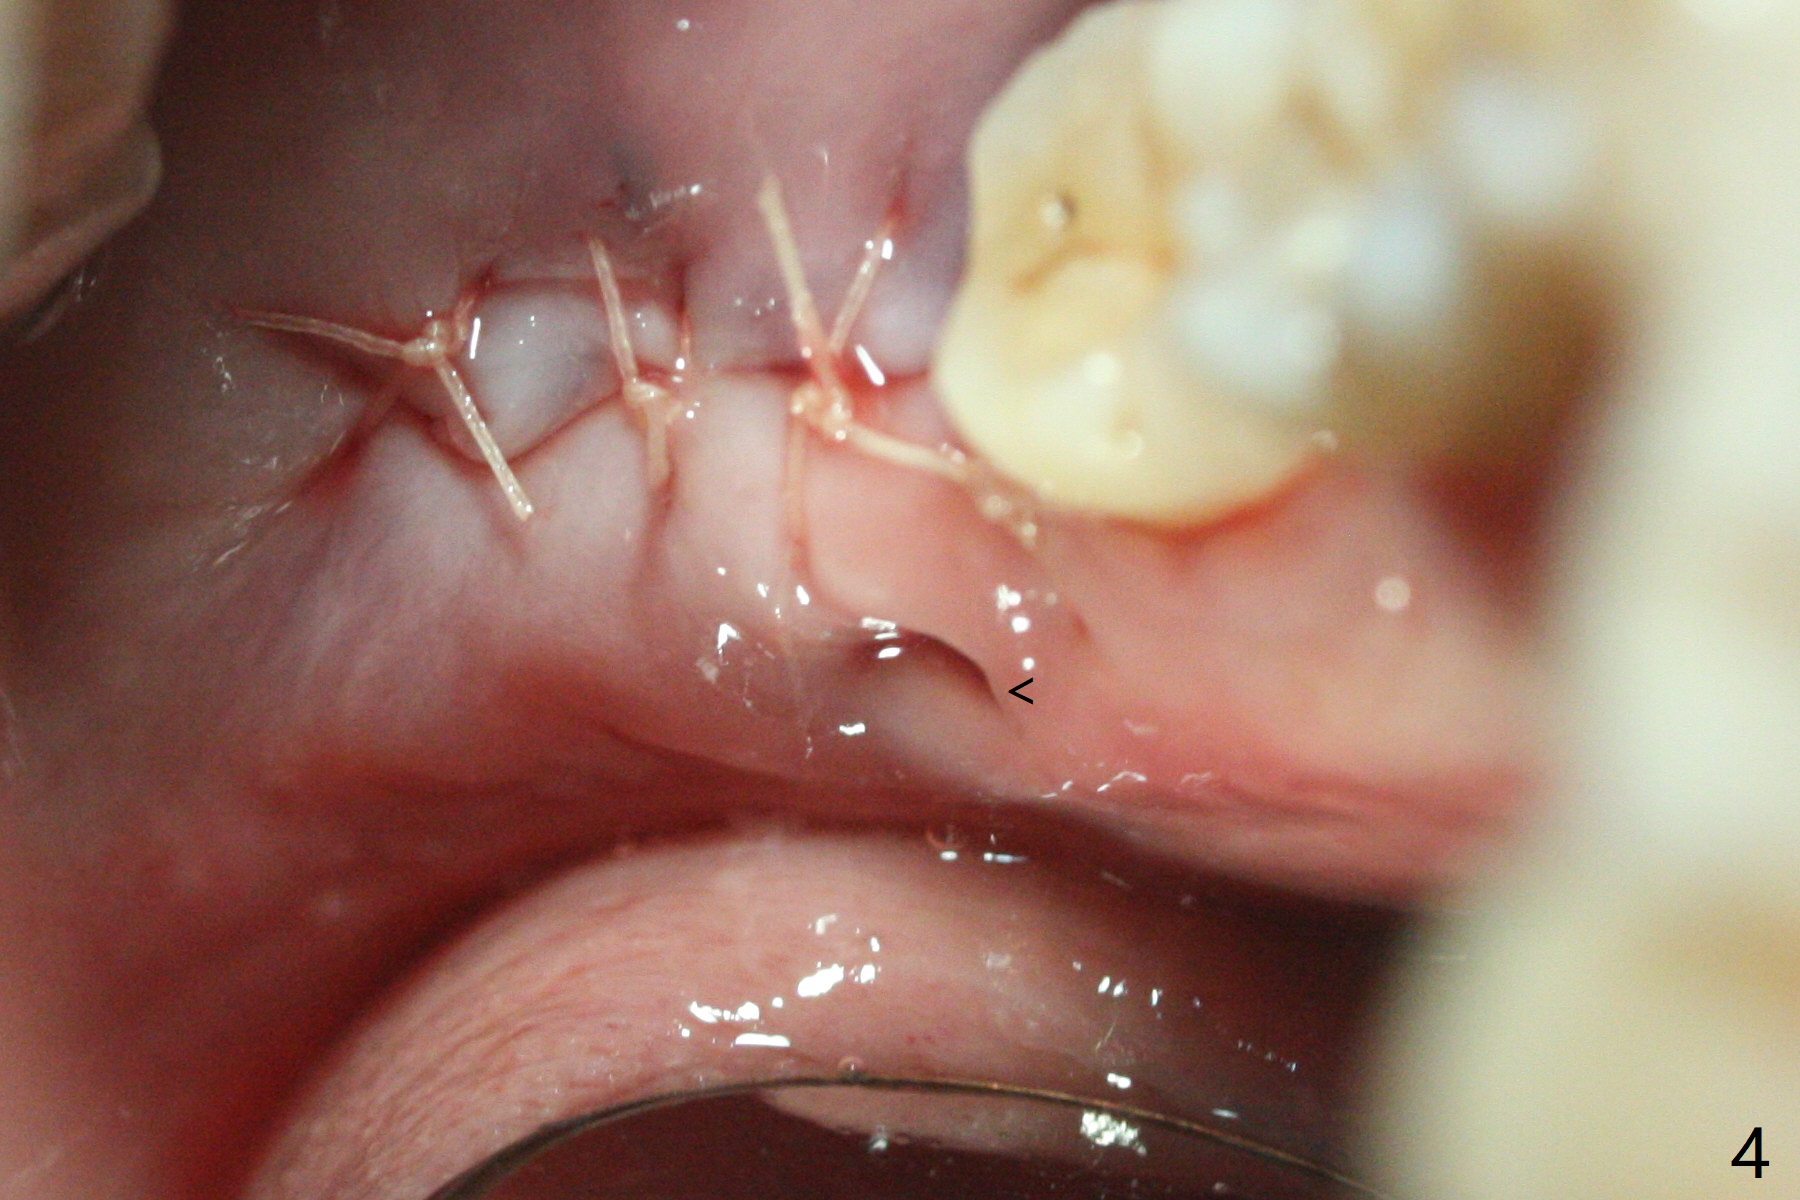

65岁女,南方人(广州),主诉左下肿胀,8舌侧粘膜穿孔(图一(舌侧观):<),初步问诊,回答:“全身没问题”,详细问诊:骨质疏松,静脉注射Reclast两年,准备拔除使用PRF修复缺损,全景片显示7远中骨质吸收严重(图二),因此8拔出后,牙槽窝塞入胶原塞(图五:C),将粘性骨粉放置7近中,远中(图五:白*)以及颊侧(黑*),把一片PRF膜覆盖骨粉(7颊侧,8牙槽窝口),另外一片放置于8舌侧穿孔(图四:箭头)颊侧,促进愈合,然后使用4-0 PGA缝合(图三(颊侧观),图四(舌侧观))。术后5天用钢丝(图六:*)和树脂固定松动牙,并且降低咬合。舌侧穿孔正在愈合(图七:>)。虽然术后三周智齿伤口裂开,但是没有症状,病人满意第二磨牙不再松动(图八),开始深洗。下次复诊拍摄根尖片观察骨质愈合。术后二个月第二磨牙远中没有骨质再生(图九),临床上远中牙根暴露。